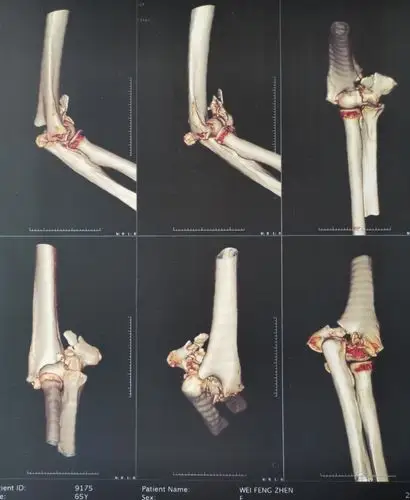

左侧肱骨髁上骨折一例

肱骨髁上粉碎性骨折,肱骨颈粉碎性骨折!

肱骨髁间骨折切开复位手术治疗